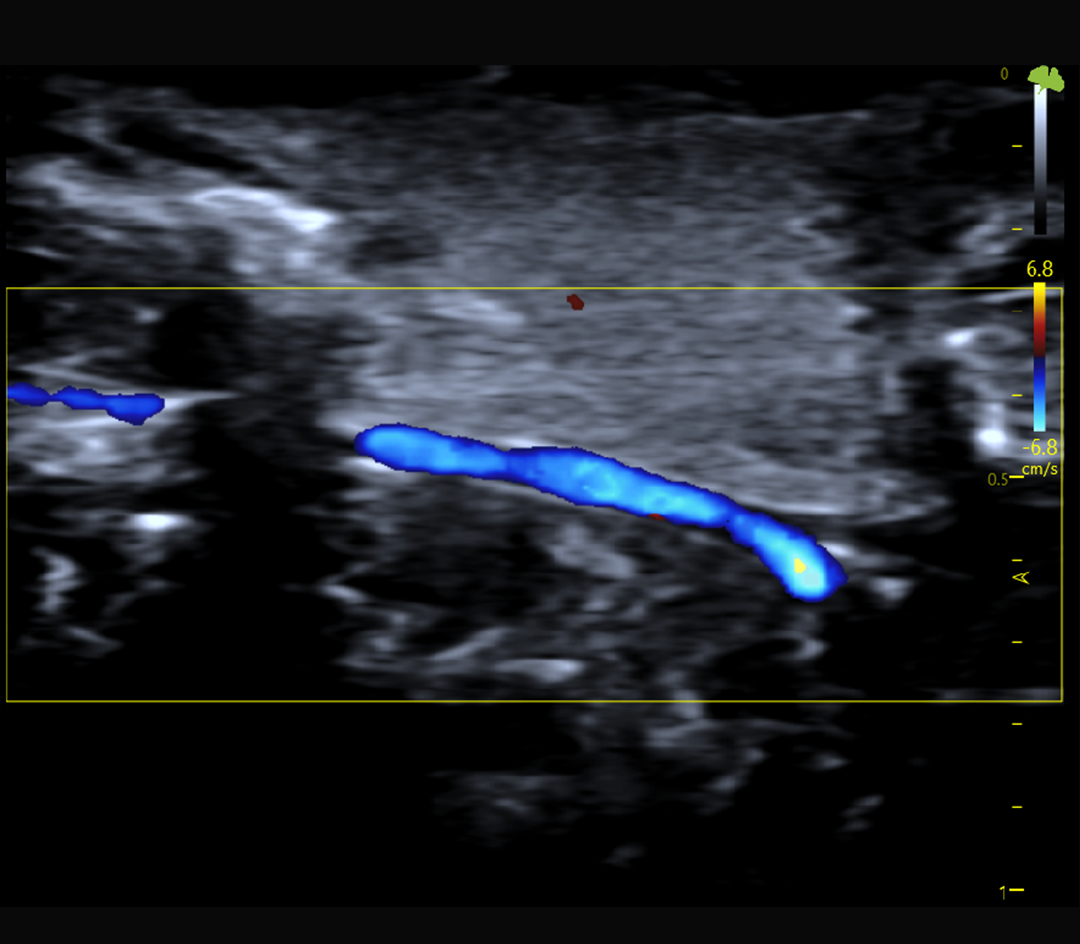

Hémodynamique et flux sanguins

Doppler couleur, pulsé et puissance

Doppler couleur, Doppler pulsé et Doppler puissance

Résultat : une imagerie fine, stable et quantitative, adaptée à l’étude de la fonction cardiovasculaire, du flux sanguin et des structures tissulaires complexes.